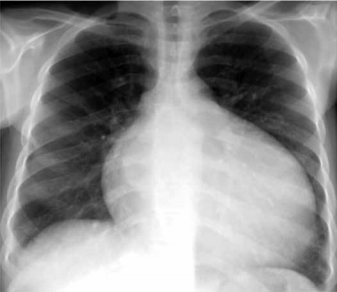

Mulher de 33 anos de idade refere febre, dispneia e dor torácica à esquerda há 3 dias. Nega tabagismo, etilismo ou patologias prévias. Exame físico: PA: 110 x 70 mmHg, FC: 96 bpm, FR: 18 ipm, T: 38,9 ºC e saturação arterial de O2: 94%; cardiovascular: normal; pulmão: crepitações em 2/3 inferior do hemitórax esquerdo. Radiografia realizada é mostrada a seguir.

O tratamento antimicrobiano inicial correto é